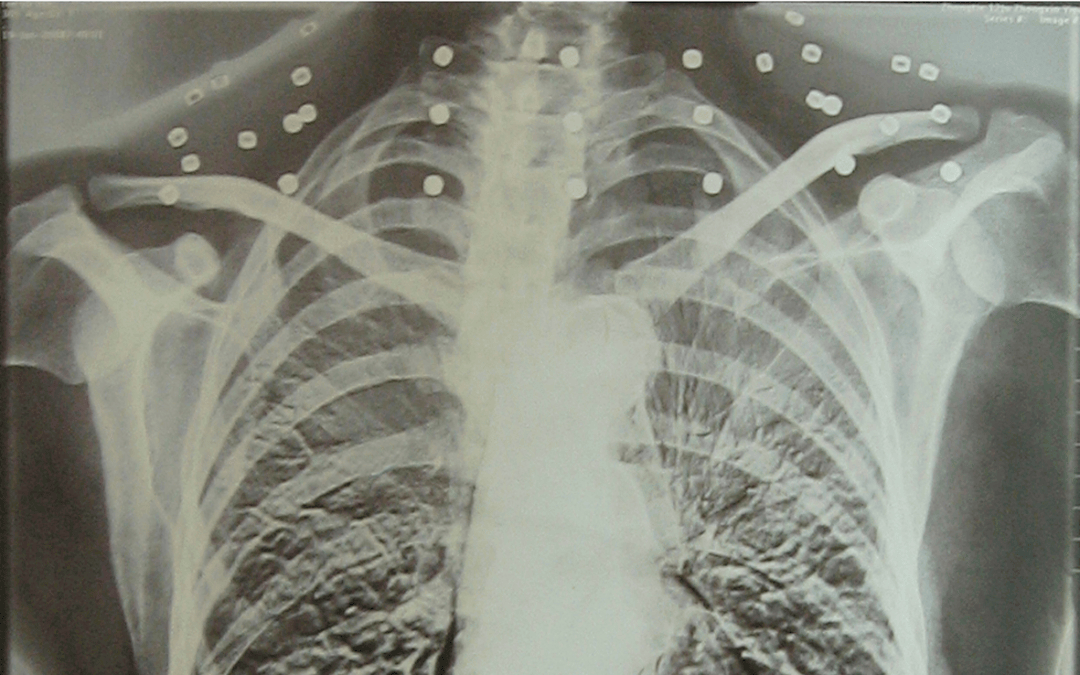

这张照片

是今年82岁的吴以先老人

拍摄的一张CT照

但实际上是

吴以先的颈部和腹部

共分布着33枚弹片

但是打进身体里的弹片

一直留在了体内

他体内的弹片都没有取出

但吴以先不考虑取出弹片

在他看来

这是他与战友并肩作战的见证

是他的勋章

与吴以先身上那33枚弹片

一起永远烙印在他心中

33枚“军功章”

是一名军人的光荣